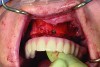

Pre-treatment smile of patient with terminal dentition.

Figure 17

The patient’s intraoral condition.

Figure 18